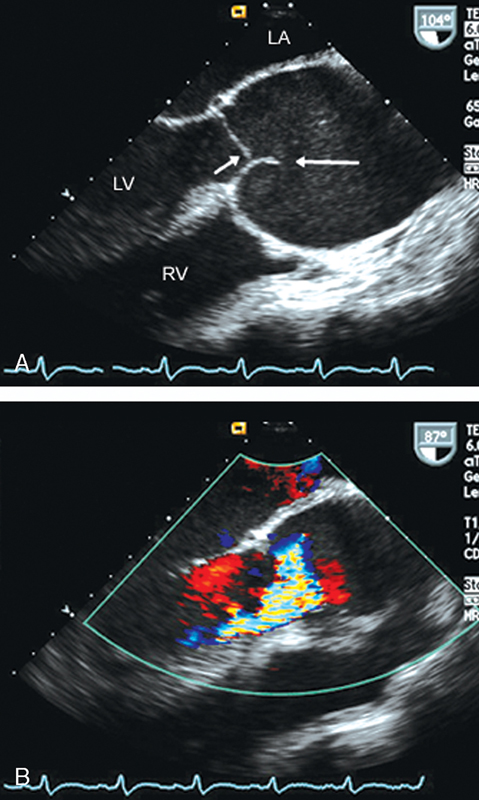

فحوصات تشخيصية لبعض امراض القلب والشرايين التاجية